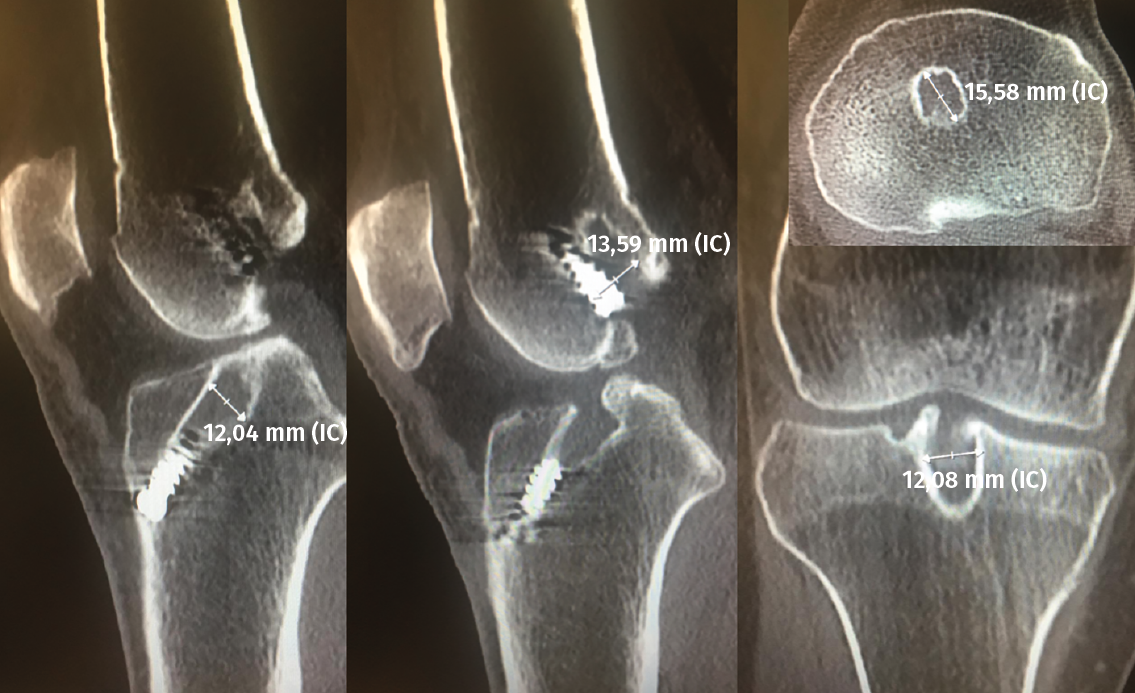

El estudio mediante TC, tanto en 2D como en las reconstrucciones actuales en 3D, va a ser de gran utilidad para poder identificar la posición de los túneles óseos tibial y femoral, la dirección de ambos y, finalmente, el grado de dilatación y la morfología de los mismos. Estos aspectos van a ser claves para poder planificar la cirugía de revisión en uno o dos tiempos (Figuras 3 y 4).

Figura 3. La tomografía computarizada en 2D mediante cortes axiales, coronales y sagitales permite conocer tanto la dirección como la morfología de los túneles previos, así como medir el grado de dilatación de los mismos para planificar la cirugía de revisión.

Figura 4. Actualmente, la reconstrucción en 3D de la tomografía computarizada permite comprender mejor la localización tridimensional de los túneles óseos.

En cuanto al grado de dilatación de los túneles óseos, la mayoría de los autores consideran que una dilatación de los mismos superior a 12-14 mm hace recomendable realizar la cirugía en dos tiempos(29,30,31). No obstante, algunos trabajos más recientes no observaron diferencias significativas comparando los resultados funcionales en recambios en un solo tiempo con presencia de túneles óseos superiores e inferiores a 12 mm y con un seguimiento de 5 a 15 años(32).